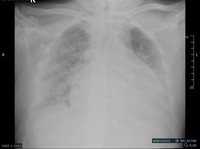

The image shows a small cohesive cluster of mesothelial cells with characteristic cell-to-cell windows. The cells are large with abundant basophilic cytoplasm and central round nuclei containing prominent nucleoli. Mild nuclear atypia is present, consistent with reactive changes. The background is hemorrhagic with numerous red blood cells. Overall, the features are in keeping with reactive mesothelial cells.